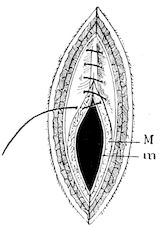

| Prolapsus and inversion of the rectum | 743 | |||

| Suture of the vulva | 768 | |||

| Section of the sphincter of the teat | 770 | |||

| Dilatation of the orifice of the teat | 770 | |||